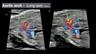

Anomalies of the Great Vessels 3: Aortic Arch Abnormalities

Anita J. Moon-Grady, M.D.